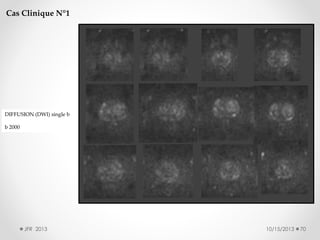

Cas Clinique N°1

DIFFUSION (DWI) single b

b 2000

JFR 2013